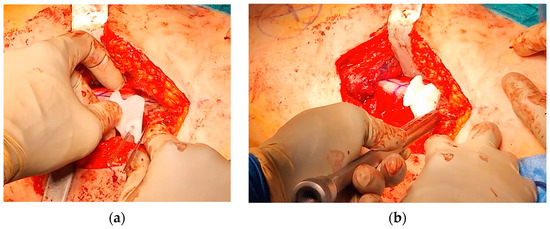

2.2. Surgical Procedure